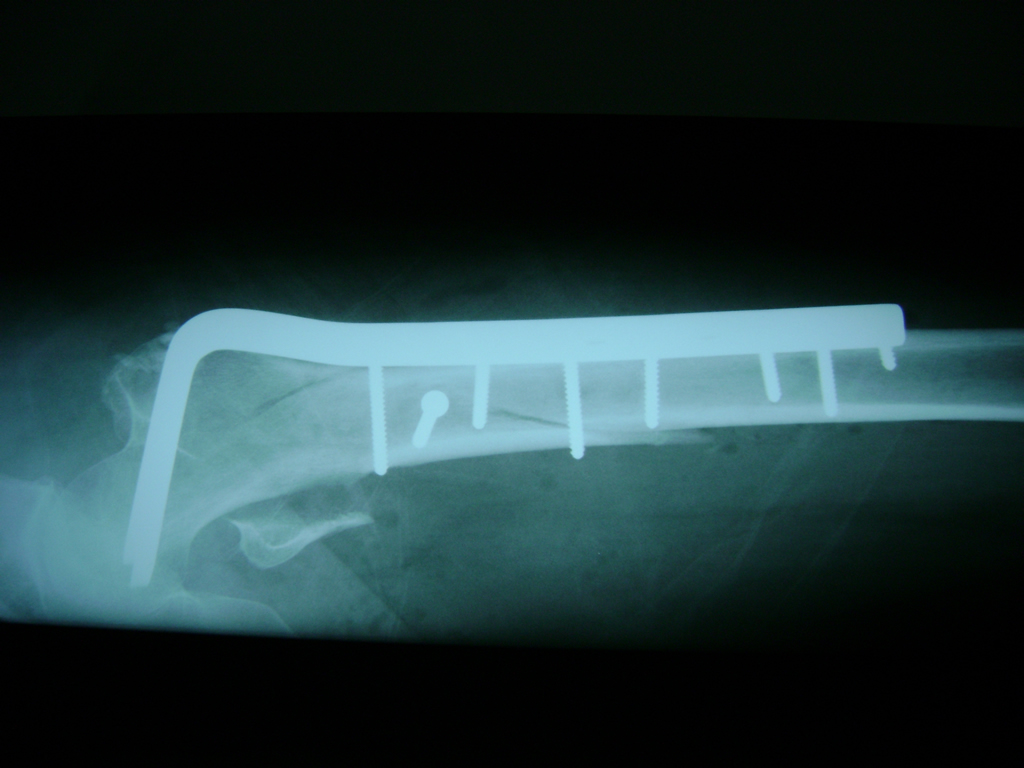

La cirugía de fractura de cadera se realiza para reparar una ruptura en la parte superior del hueso del muslo. Este hueso se denomina fémur.

Es parte de la articulación coxofemoral. Si una fractura de cadera no recibe tratamiento, es posible que deba permanecer en una silla o en la cama.